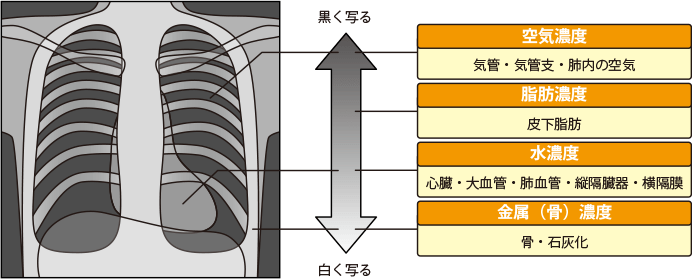

通常、立位で胸部の正面や側面からX線を当てて撮影します。X線は人体を透過する際に骨や臓器などのさまざまな組織に吸収されるため、フィルムには透過後のX線が検出されます。X線像は組織性状ごとのX線透過性(吸収度)の差を白〜黒の色調で表したもので、大きく4つに分けられます。

X線の撮影写真では、骨や心臓は白く写り、肺は黒く写ります。肺の中に白い影があるときには肺がんが疑われます。ただし、肺炎や肺の良性腫瘍などの病気によっても白い影が出るので、X線検査だけで肺がんであると確定することはできません。逆にいうと、X線検査で異常がなかったから肺がんではないとも言い切れません。